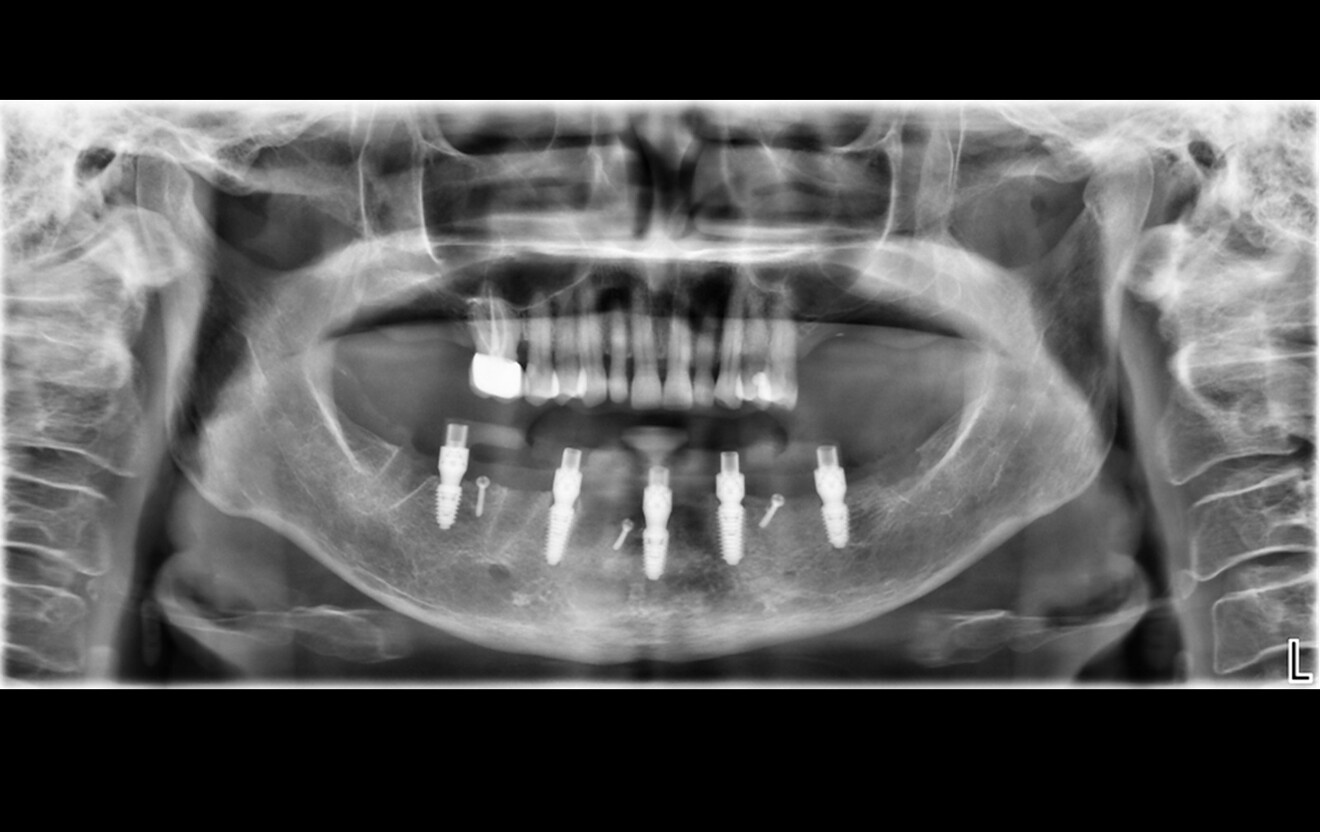

Fig. 1a: Pre-op panoramic radiograph. (All images: Dr Ádám Kapai, Dr Tamás Chikány, Tamás Csornai)

Intra-oral examination revealed compromised mandibular dentition, an old fixed prothesis, missing posterior teeth on the left side, periodontal involvement and gingival inflammation. A panoramic radiograph was obtained, and the findings were reported to the patient (Figs. 1a & b; 2a & b). Both mandibular canines had visible periapical radiolucencies. A CBCT scan was performed for a more detailed assessment of the alveolar bone anatomy (Figs. 3a & b). Temporomandibular joint examination revealed no indication of dysfunction (crepitus, clicking or pain).